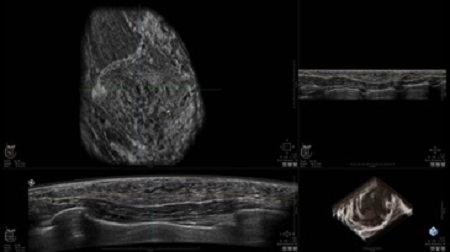

GE INVENIA ABUS 2.0

GE INVENIA ABUS – это современный УЗИ аппарат, который создан для точной и эффективной диагностики сканирования с высокой плотностью молочных желез. Выявляемость патологий раковых и предраковых стадий заболевания составляет 55%, что в конечном счете позволяет ставить врачу точные и своевременные диагнозы. Традиционные методы использования маммографии не показывают такой выявляемости, ограничиваясь лишь 3-38%.

УЗИ-аппарат GE INVENIA ABUS позволяет проводить максимально операторонезависимые процедуры, что значительно снижает риск неправильной постановки диагноза и сопутствующие издержки на обработку информации. Система готовит отчет в течение 3-х минут после сканирования, это безусловное преимущество по сравнению с обычным УЗИ сканером.

Данное устройство классифицируется, как стационарное, используемое в многопрофильных клиниках, женских консультациях, медицинских центрах. Вес без учета дополнительного оборудования составляет 105 кг. Удобная колесная база позволяет оперативно маневрировать в ограниченных пространствах, в том числе передвигать устройство в коридорах клиники. Большой 17-ти дюймовый монитор с широкими углами обзора выводит максимально качественную картинку в формате Full HD.

• Получение объемных 3D изображений с возможностью покадрового просмотра

• Отображение объемных 3D ультразвуковых изображений, которые состоят из традиционных поперечных и воссозданных коронарных и сагиттальных проекций

• Возможность отображения полного 3D изображения